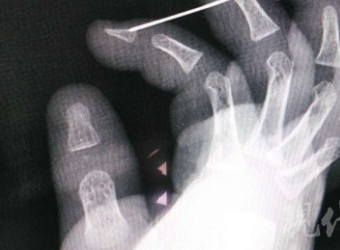

现代快报讯(记者 李伟豪 通讯员 李娜)11月7日上午,徐州某医院手外科三病区的病房走廊内,一位老奶奶怀中抱着满脸泪痕的一岁患儿小宝在拼命的哄着,小宝的右手上,包裹着一层又一层的纱布,身旁的年轻女子正给它贴胶带,她是小宝的妈妈。

秋高气爽,正是出游好时节,但伴随而来的还有意外摔伤患者的急剧增多。南都记者从深圳平乐骨伤科医院了解到,该院手外科在11月1日、2日号共收治16名新鲜手部骨折患者,较平日增幅明显。16名患者中年龄从23岁到64岁不等,都是因为走路不小心滑到、骑车摔倒、运